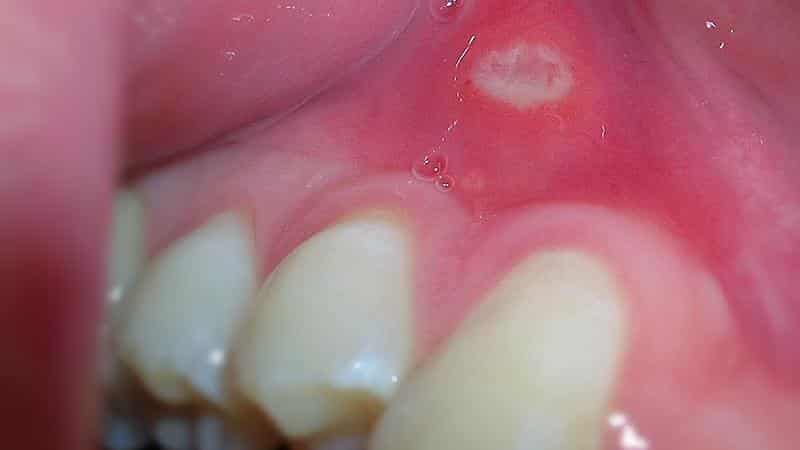

Стоматит

Стоматит – это заболевание ротовой полости, характеризующееся воспалением. Обычно оно возникает на фоне ослабленного иммунитета или инфекционного процесса. Это состояние проявляется высыпаниями на слизистых оболочках рта, а также на губах и деснах в виде мелких белых пузырьков, иногда можно заметить и гнойные образования на деснах. В некоторых случаях инфекция может сопровождаться повышением температуры тела.

Это инфекционное заболевание не проходит самостоятельно и требует адекватного лечения. При своевременном обращении к специалисту стоматит легко поддается терапии и не оставляет негативных последствий.